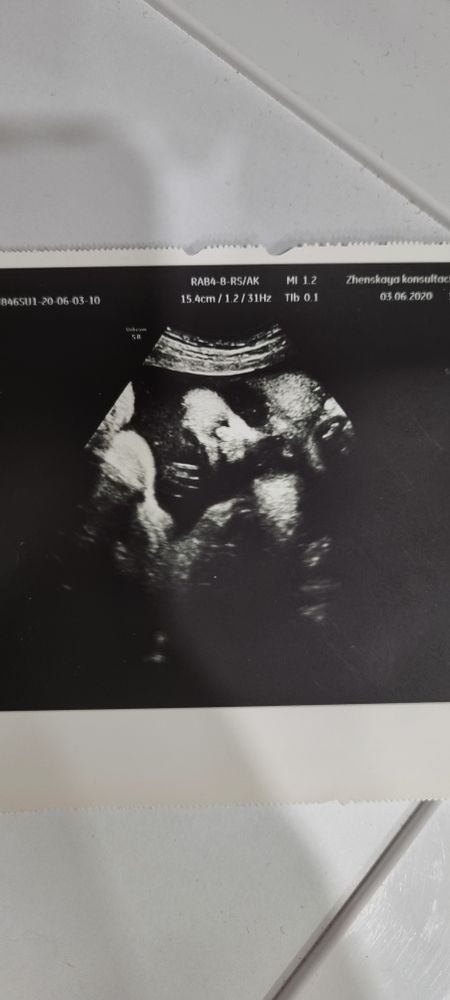

Вот снимок 3-4д на 13ой неделе

А вот на 21ой

А вот на 21ой

Я думаю если вам включат 3-4д режим, обязательно посмотрите на малыша) но если нет, вы не сильно много потеряете) а пол даже в 10Д не скажут, рано ещё) бугорок просто будет